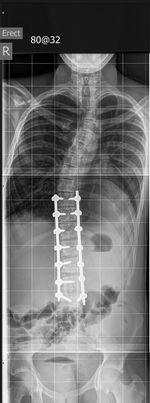

Just to show you operation #1. Hunter has come through really well.

Hunter has had the first of 4 operations. He is now home and recuperating after having his back opened up and rods and pins inserted to straighten his spine. Over the next few weeks he will pick up his guitar and thanks to you he has a new amp and other accessories necessary for rock star growth. Thanks for your support.